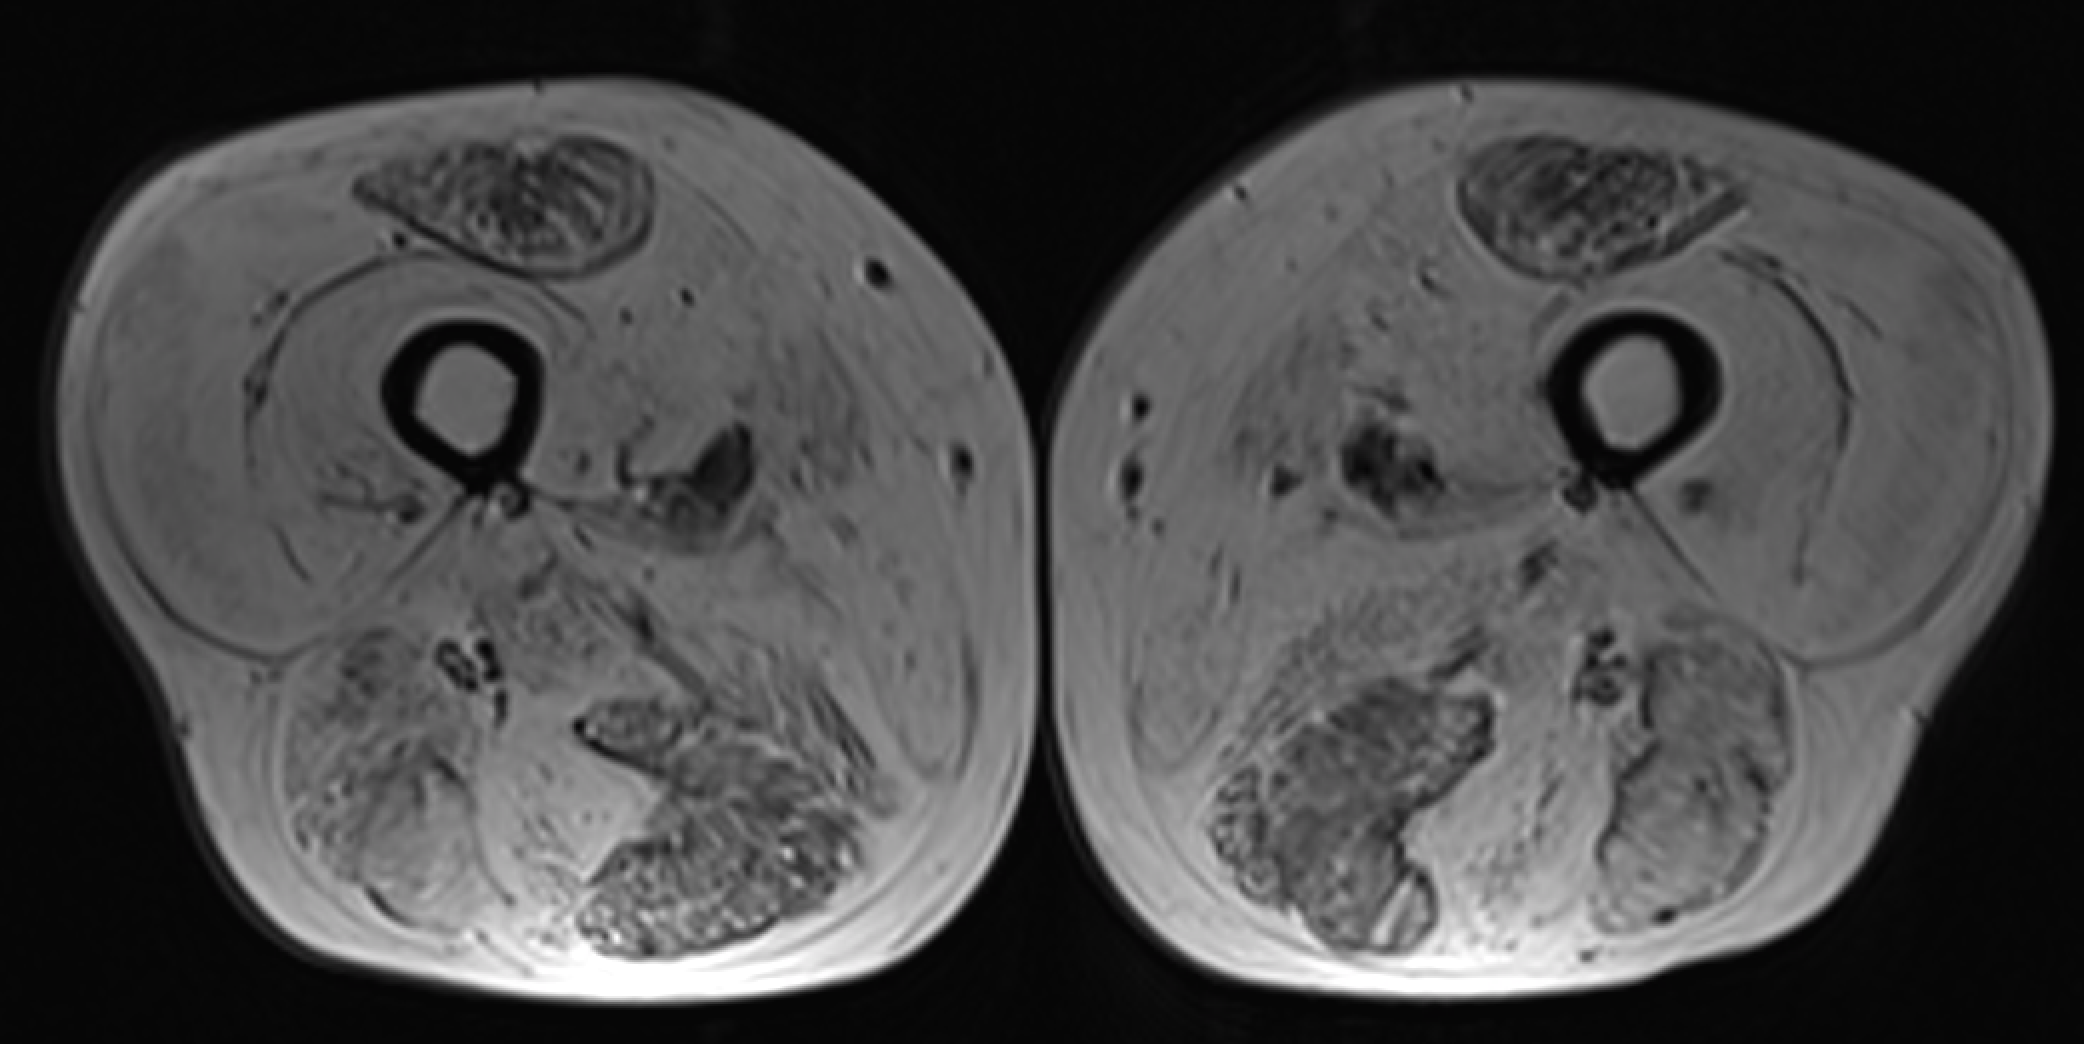

We would like to invite you to the second session on " Muscle Pain"

Dr Dimitri Amiras (Imperial College Healthcare NHS Trust) - "Dr Amiras is a substantive radiology consultant at the Imperial College Healthcare Trust and is a senior honorary clinical lecturer at Imperial College London. He is a previous alumnus of Imperial College School of Medicine and Imperial radiology training programme. He obtained a fellowship in musculoskeletal radiology in Fremantle Hospital, Australia and consolidated his training with observerships at the AMC in Amsterdam and Auckland Hospital, New Zealand. He has developed dedicated techniques for the assessment of skin perforators in lower leg reconstructive surgery, saving valuable surgical time and is a valuable member of the complex trauma team.He is an advocate for innovation and is the senior author on a paper describing the first use of the Microsoft HoloLens in Augmented Reality plastic reconstructive surgery as well as pioneering its use in radiology training. He is an engaging speaker, and has given keynote speeches for Microsoft and Cannon as well as participated in workshops for FDA a co-author on a position paper on the use of Augmented Reality in healthcare. Dr Amiras has also developed a dedicated ultrasound guided muscle biopsy technique for the investigation of muscle pathology and is skilled in the interpretation of imaging in the investigation of myopathy. He is a member of the RCR iRefer panel advising national guidelines on up-to-date imaging used across the country."